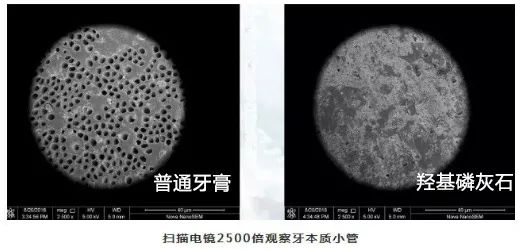

这是测试人员牙齿表面的显微镜图,在使用3天后,牙齿表面的小孔已经基本填补完成!太厉害了!

我们看了显微镜下的对比图:涂了含有羟基磷灰石成分的欧志姆牙膏以后,鸡蛋外壳密度明星增加,而涂了普通牙膏的鸡蛋,密度依然很大孔隙。